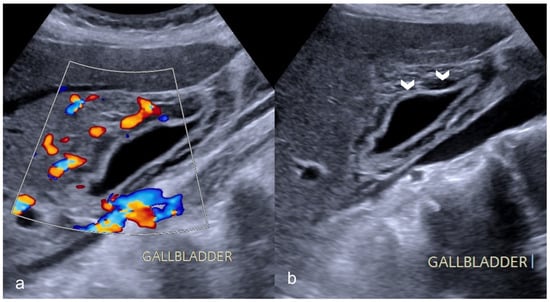

Biliary imaging findings are also encountered in patients with COVID-19 infection. In our institution, many patients presented with right quadrant pain and nausea/vomiting after a meal. In ultrasound and CT examinations, the findings included gallbladder distention, wall thickening and mural edema, pericholecystic fluid and inflammatory fat stranding with calculi and/or sludge (Figure 7 and Figure 8).

Less frequently, acalculous cholecystitis with sludge is seen in patients in the ICU, indicating cholestasis due to parenteral nutrition and/ or systemic inflammation [27,28].

Figure 7. A 69-year-old man with COVID-19 presented a positive Murphy sign. Ultrasound images showed gallbladder wall striation and increased thickness ((b)-arrowheads). The Color Doppler technique revealed hyperemia (a). No gallbladder stones were present indicating acalculous cholecystitis.